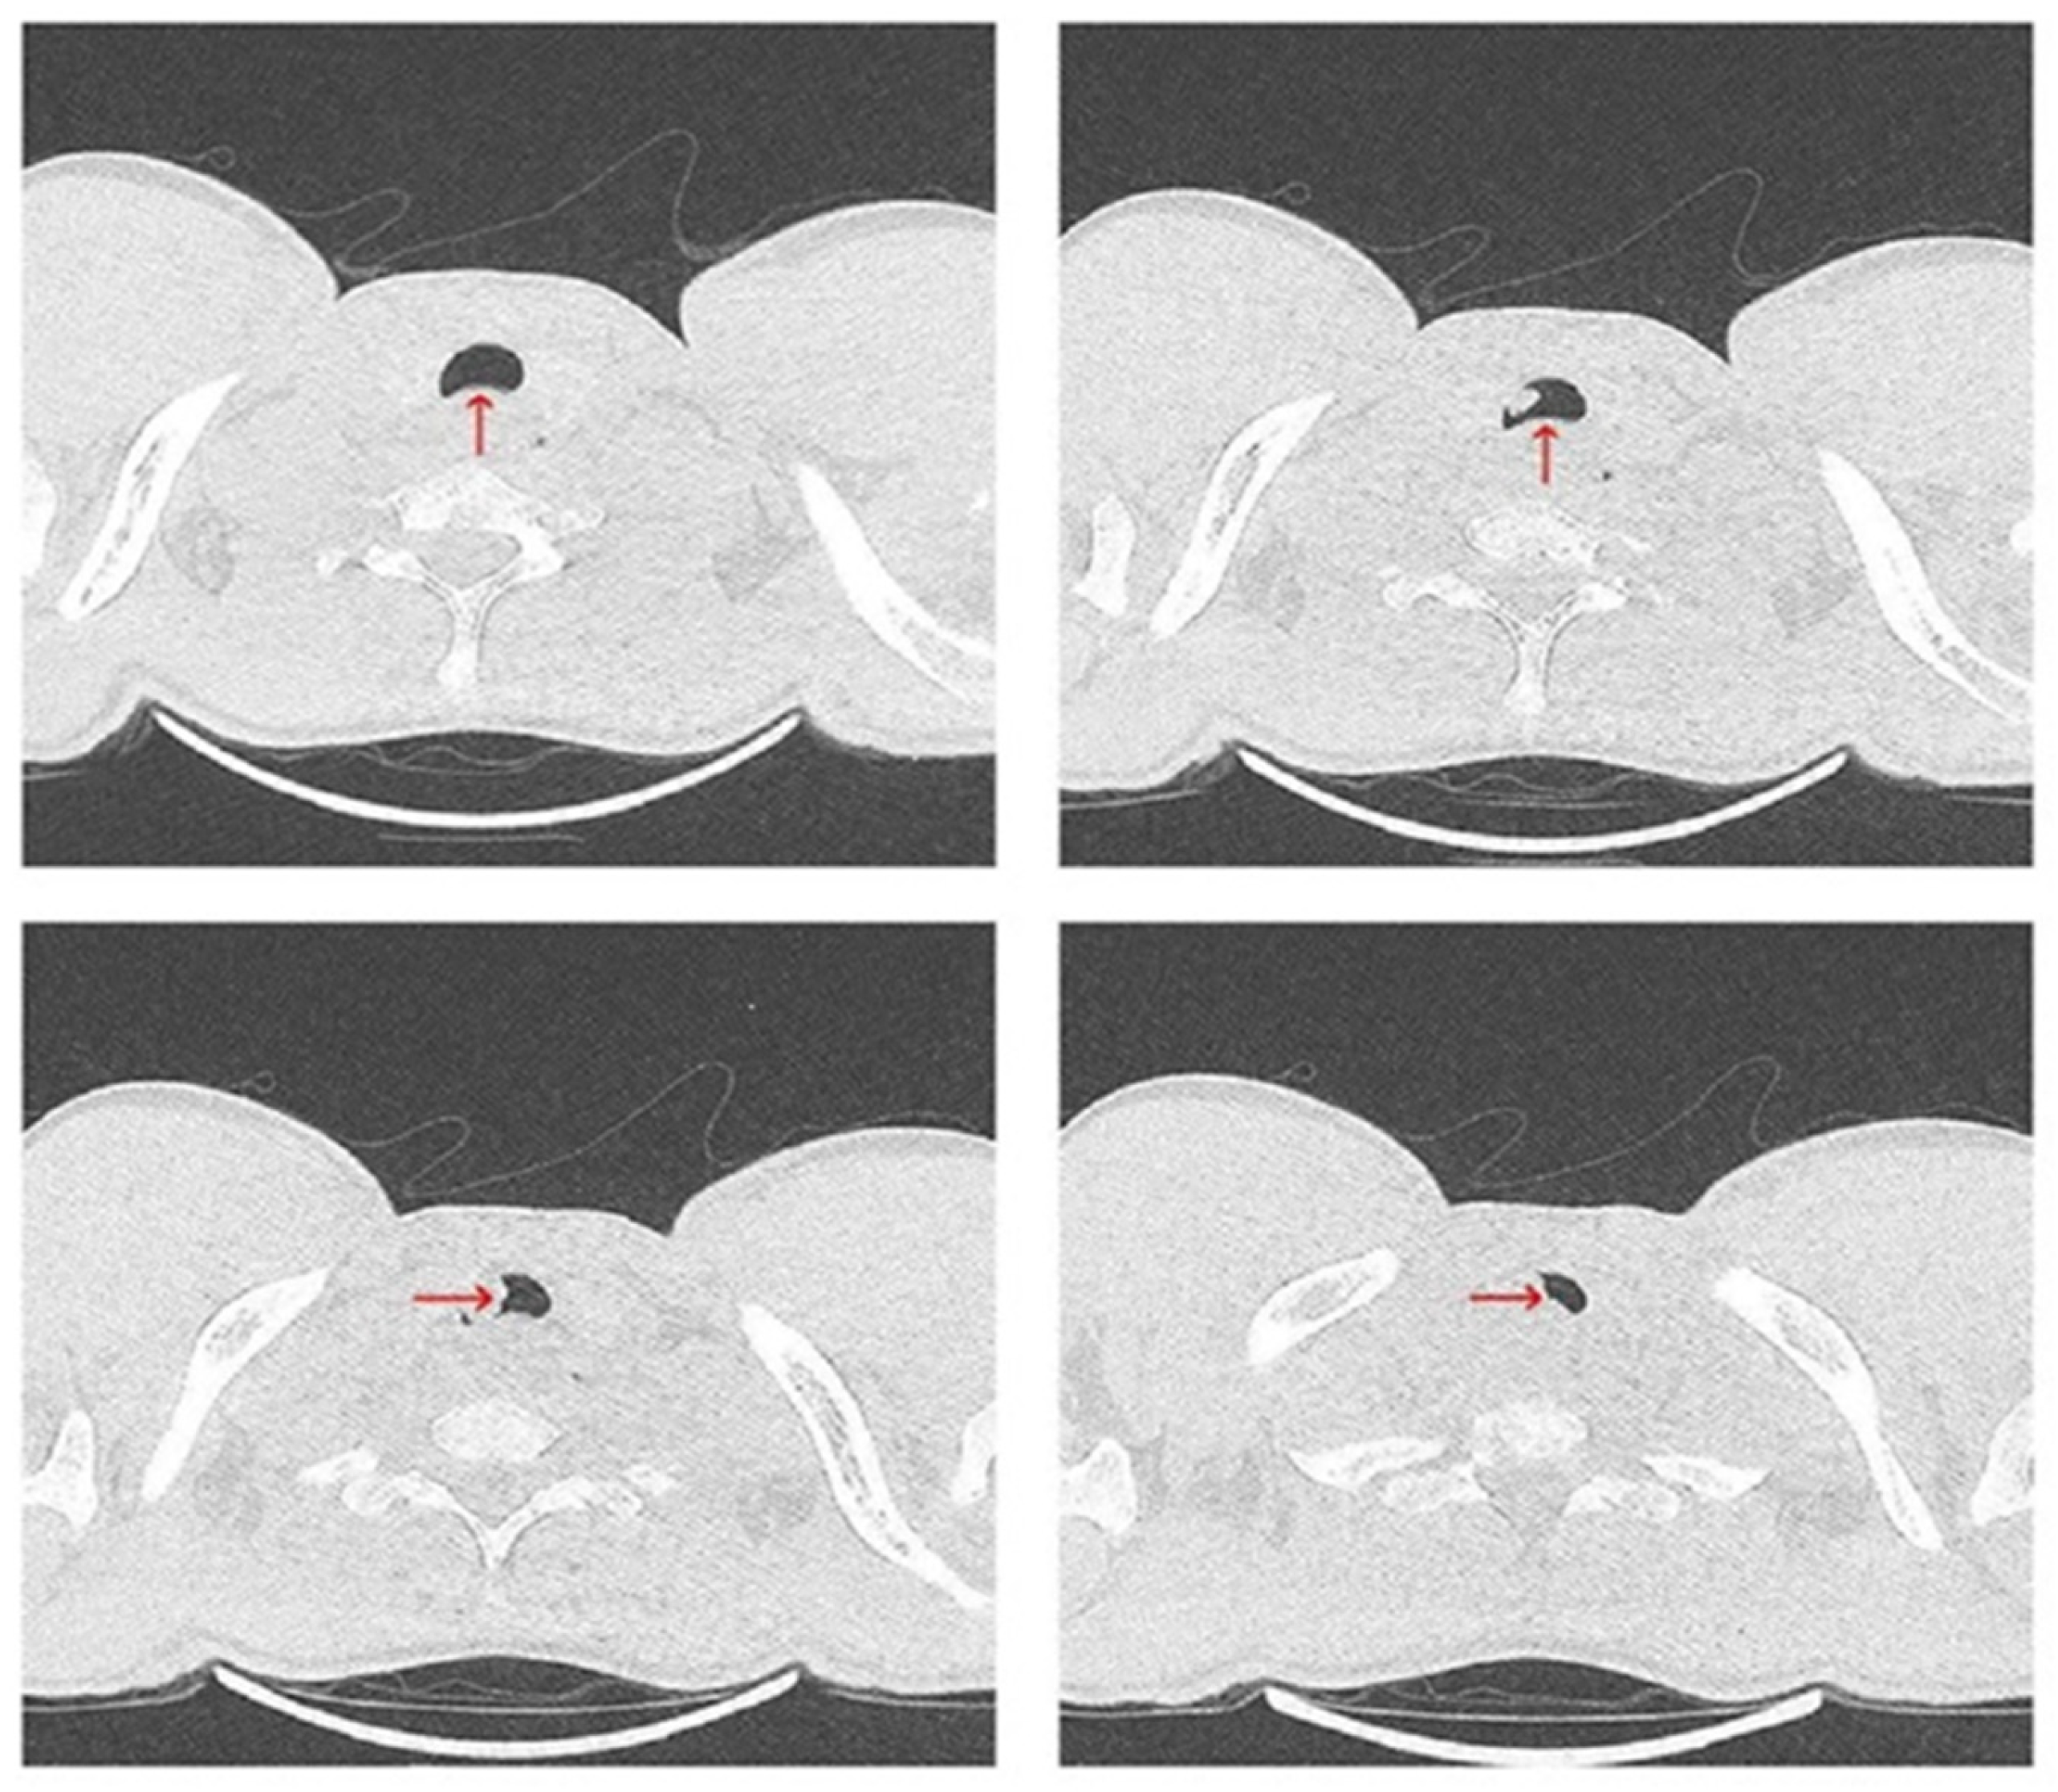

2. Case Report